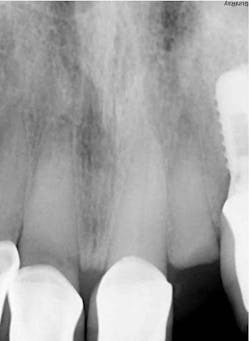

Maintaining initial stability is important when an implant is placed in a compromised extraction site, since there is less bone-to-implant contact there than in a healed site. Because of its architecture, the Ditron Ultimate implant offers a very high initial stability and strong abutment connection. The implant profile uniformly distributes the stress directly to the bone, which results in a more even distribution of force and lower long-term crestal resorption. This implant system has a good aggressive thread profile and a secure abutment connection, which are both key characteristics. The microthreads on the implant’s reverse conical neck (RCN) greatly increase the implant’s ability to resist axial displacement, and the mechanical stimulus the microthreads provide helps to preserve the peri-implant marginal bone. By inserting an Ultimate implant, 5.57 mm3 of bone will be saved compared to that of a non-RCN implant.7

First visit: Extraction and immediate implant placement, immediate placement of the final abutment prepared intraorally, and then a provisional out of function.

The implant was allowed to heal for two months before impressions were taken. The final zirconia crown was delivered two weeks later (figure 6).